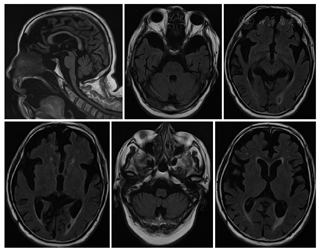

辅助检查结果:5月2日行血、尿、便常规,生化,肿瘤标志物检查,结果均正常。5月3日行心脏和腹部超声未见明显异常。头颅MRI(5月11日)示:双侧侧脑室周围及额顶叶皮质下腔隙性梗死、缺血灶;脑萎缩(图1)。24 h脑电图(5月10日):清醒期两侧大脑半球轻度慢波活动,睡眠期见少量散发及短阵尖波、尖慢波,颞顶区偏胜,5月10日晨视频见肢体抽搐发作,同时见右侧颞区短暂可疑尖波发放,痫样放电可能(图2)。胸部CT(5月1日):慢性支气管炎样改变伴两肺感染,两下肺间质略增生;主动脉硬化,左心室增大;两侧胸腔少量积液;两肺尖胸膜增厚、钙化(图3)。

The recovery sequence of fluid inversion on cranial magnetic resonance imaging of the patient showed bilateral lacunar infarction and ischemia around ventricle and subfrontal-parietal cortex, brain atrophy